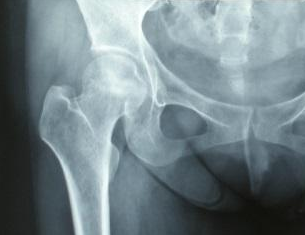

股骨头坏死在不同的阶段应当给予不同的治疗方案

股骨头坏死的症状有哪些?河南骨科医院为您详细介绍

河南骨科医院介绍对于股骨头坏死的症状,主要还是体现在以下几个方面。早期容易出现髋关节…[详情]

怎么看左侧股骨头坏死,郑州骨科专科医院为您介绍股

郑州骨科专科医院为您介绍一般对于左侧股骨头坏死早期,主要还是表现为髋关节的疼痛症状,…[详情]